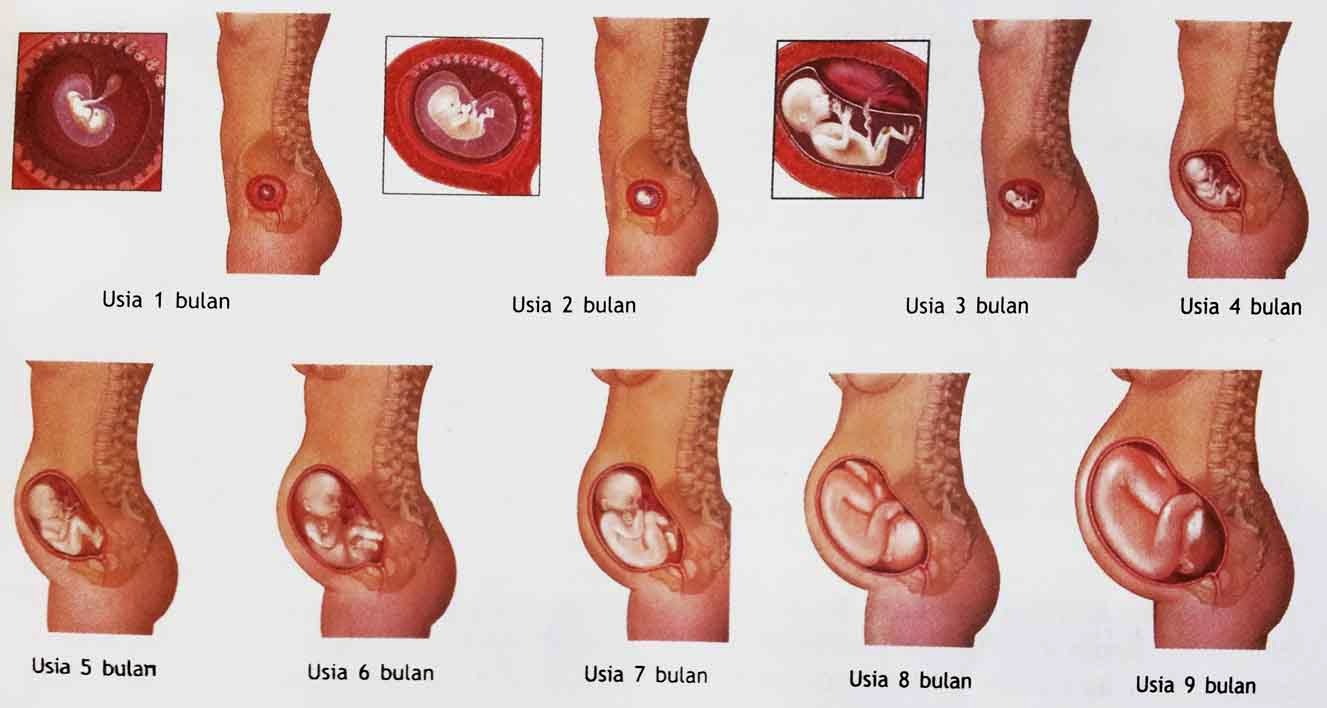

Perkembangan Janin Minggu Ke Minggu 1 40 Gambar Lengkap

Perkembangan Janin Minggu Ke Minggu 1 40 Gambar Lengkap

Perkembangan Janin Minggu Ke Minggu 1 40 Gambar Lengkap

Perkembangan Janin Minggu Ke Minggu 1 40 Gambar Lengkap